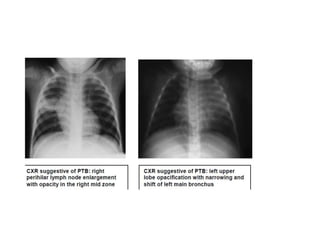

Radiological diagnosis

Chest X-ray

CXR remains an important tool for diagnosis of PTB in children who are sputum smear

negative or who cannot produce sputum

The following abnormalities on CXR are suggestive of Tb :-

• Enlarged hilar lymph nodes and opacification in the lung tissue.

Radiological diagnosis Chest X-ray CXRremains an important tool for diagnosis of PTB in children who are sputum smear negative or who cannot produce sputum The following abnormalities on CXR are suggestive of Tb :- • Enlarged hilar lymph nodes and opacification in the lung tissue. • Miliary mottling in lung tissue • Cavitation (tends to occur in older children) • Pleural or pericardial effusion – though seen on CXR – are forms of extra pulmonary TB that tend to occur in older children • The finding of marked abnormality on CXR in a child with no signs of respiratory distress (no fast breathing or chest indrawing) is supportive of TB

Primary Tuberculosis onCXR 1.GangliopulmonaryTB ( Characterized by the presence of mediastinal and/ or hilar lymphadenopathy and parenchymal abnormalities, the Ghonfocus 2.TuberculousPleuritis 3.MiliaryTB 4.Tracheobronchial TB